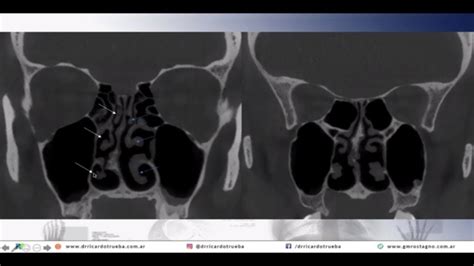

En la TC se distingue una lesión sólida que ocupa meato medio, superior y común derechos, además del hemicuerpo etmoidal, con extensión a lámina papiracea, lámina cribosa y músculos recto medial y oblicuo mayor. También se objetiva infiltración de la porción superior del septo nasal, con la masa creciendo dentro de la fosa craneal anterior, sobre el techo de la órbita. Se completa el estudio con RMN de senos paranasales, confirmando los hallazgos anteriores.